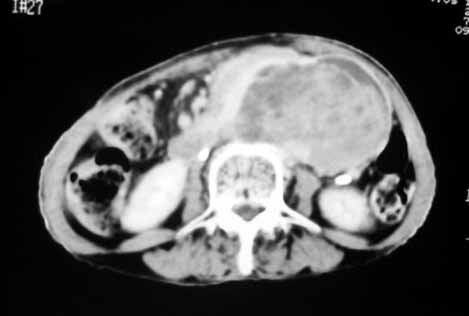

以下是引用天南地北在2007-4-30 17:42:00的发言:[br]增强扫描显示腹主动脉给包绕、推移。肿块不规则强化,[br]修正我在平扫的诊断[br]支持考虑:间叶源性肿瘤可能性大

以下是引用余辉在2007-4-30 18:01:00的发言:[br]病灶前方的条状增强影是什么?若是胰腺,位置似乎有点低,若是十二指肠,似乎又不诫该是那样强化,姑且将其看作胰腺吧,那么考虑来源于胰腺粘液囊腺瘤可能性大,其次考虑来源于肠系膜或者后腹膜的肿瘤如平滑肌肉瘤,异位嗜铬细胞瘤及淋巴瘤等。

以下是引用zyx168在2007-4-30 23:24:00的发言:[br]考虑:间叶源性肿瘤可能性大